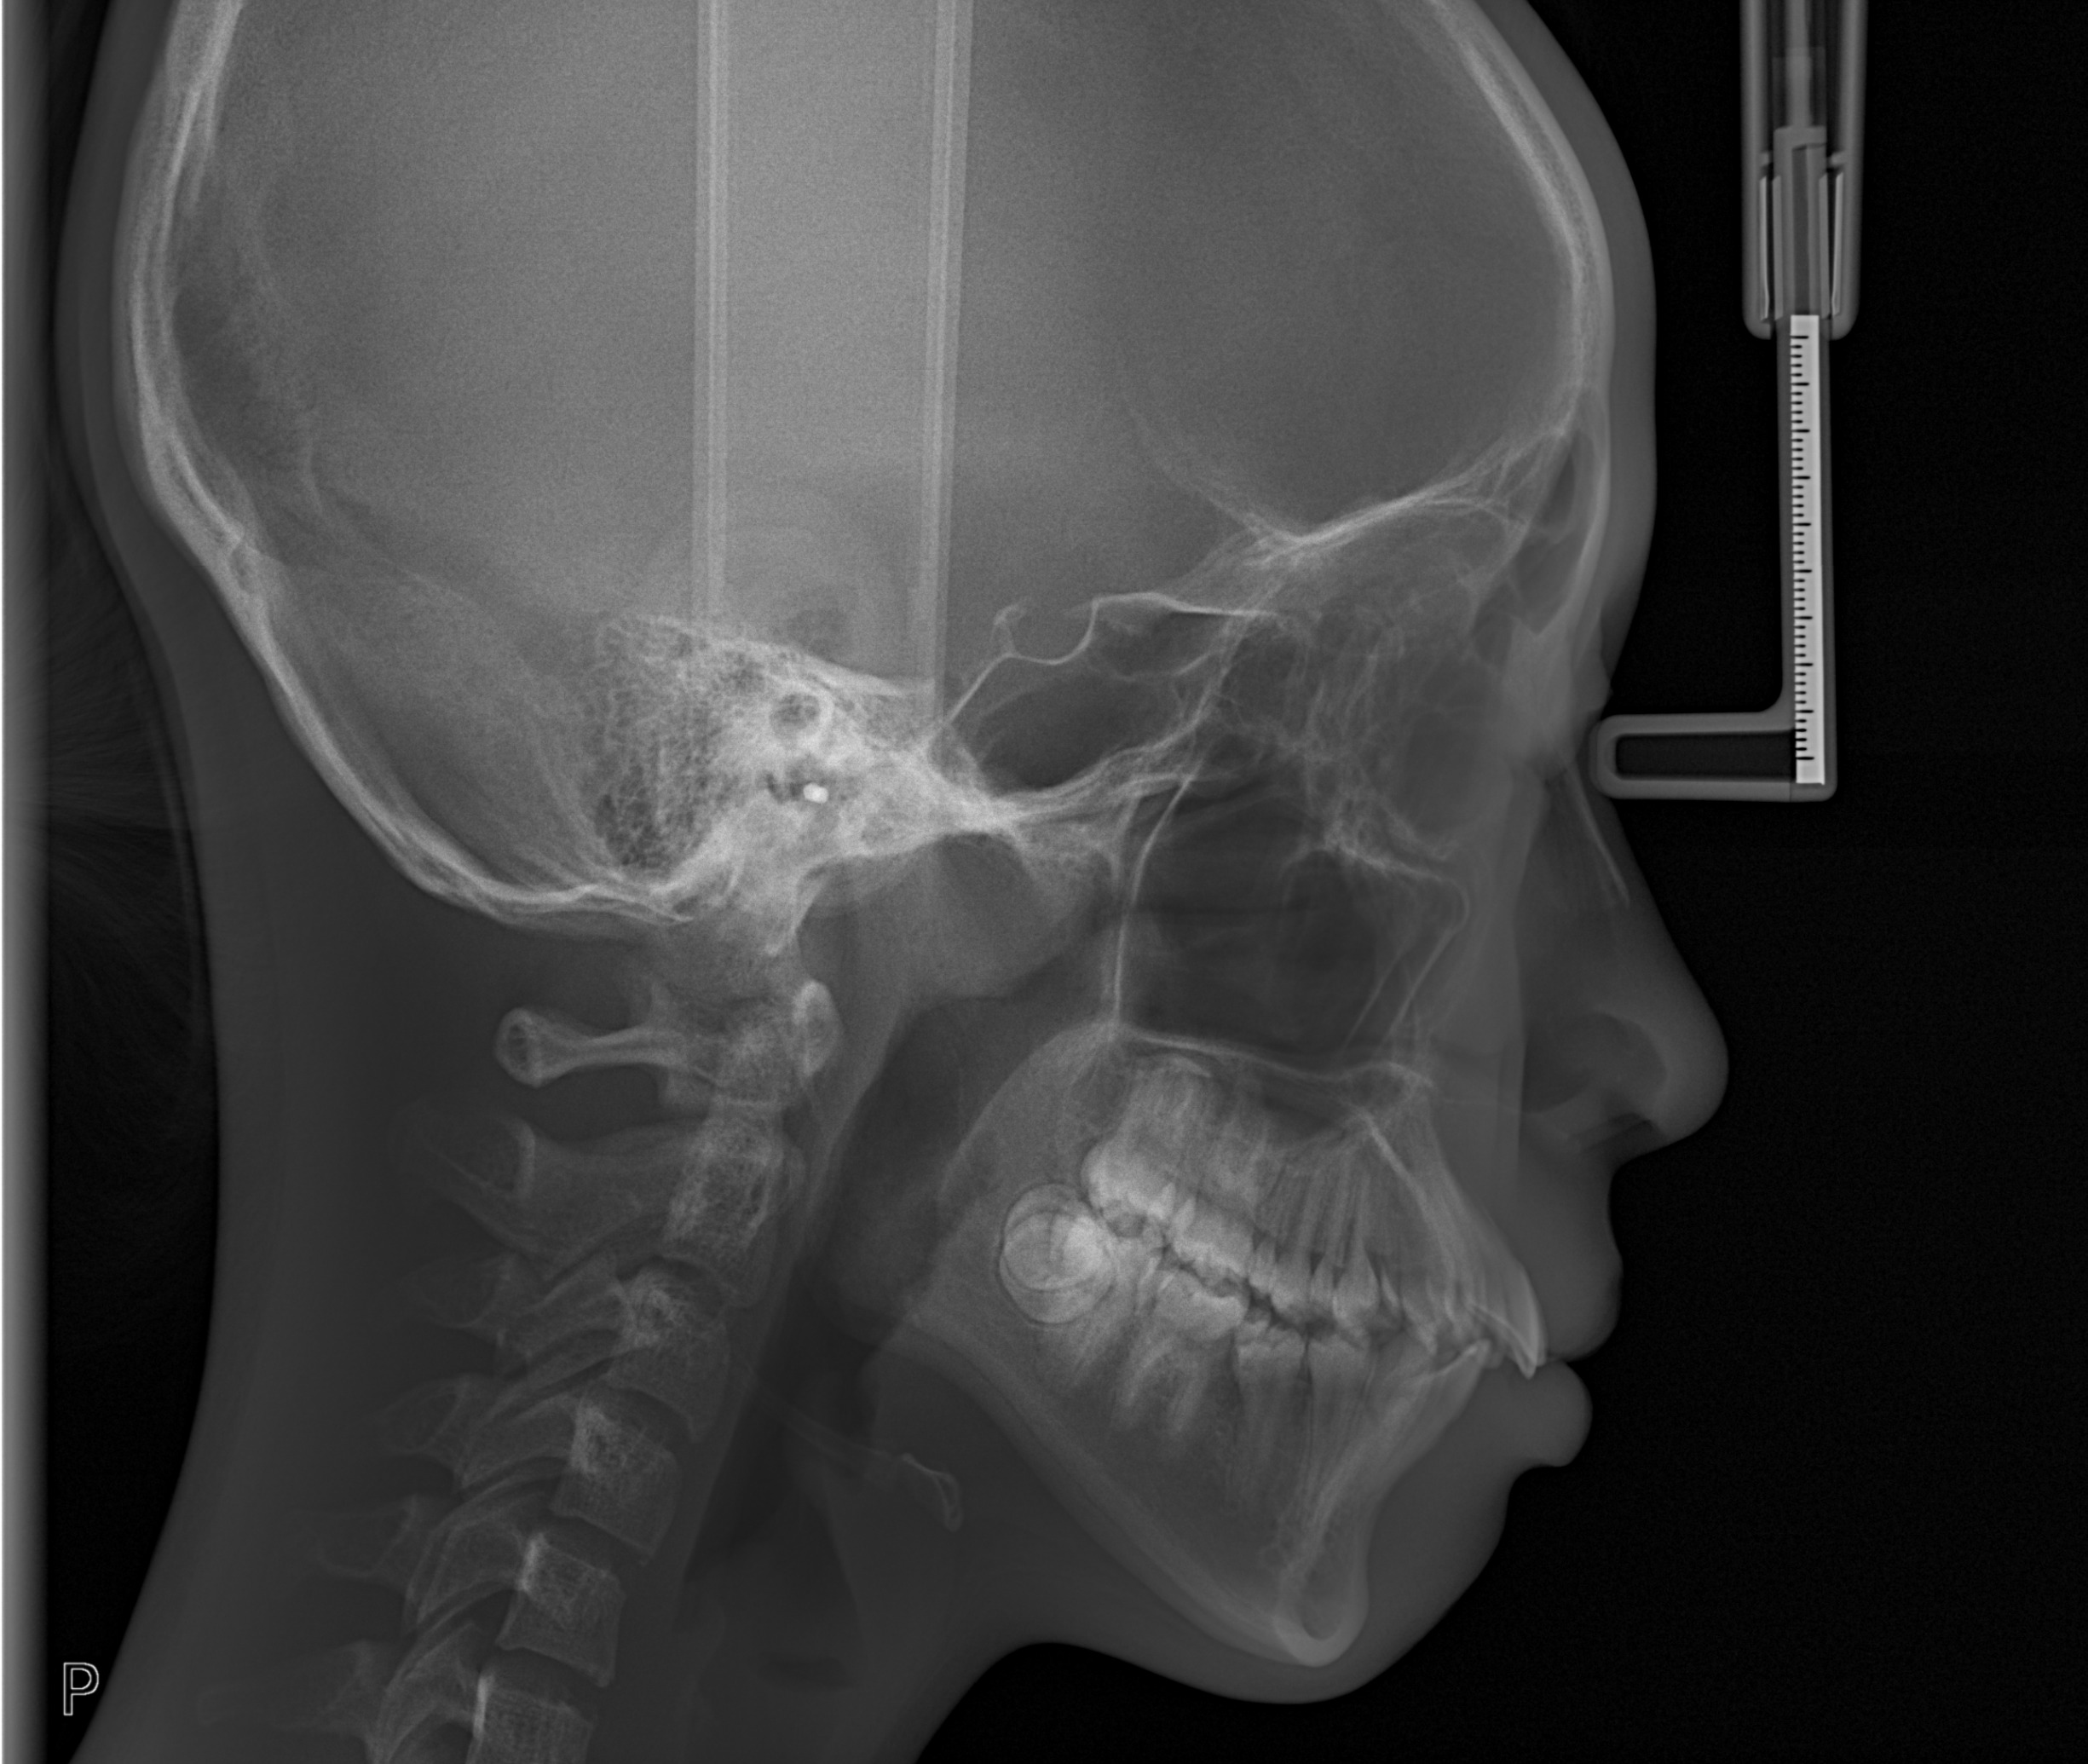

Radiografi lateral cephalometric adalah salah satu metode utama dalam ortodonti untuk menilai hubungan antar struktur rahang dan wajah. Dengan analisis sudut-fasial seperti model Downs, dokter

CBCT pada Penatalaksanaan Cleft Lip and Palate (Bibir Sumbing)